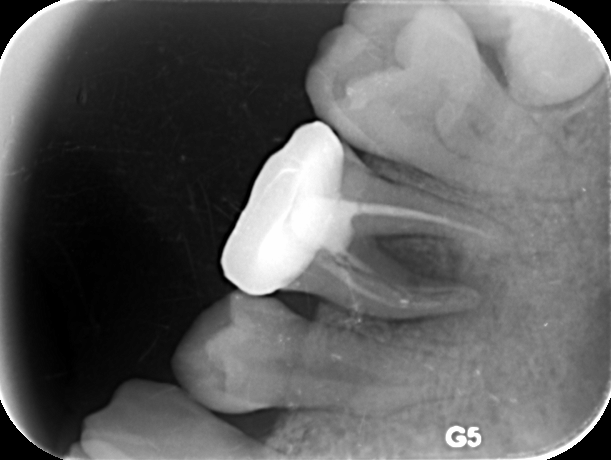

5、检查时可能见到较深的龋洞,用探诊探查时牙齿疼痛明显。或可能发现畸形中央尖、畸形舌侧窝等可能导致牙髓炎的情况。>>点击在线咨询详情<<

牙博士口腔采用的显微根管治疗法的成功率很高,是目前保存患牙较好的治疗方法。一般来讲,对于那些牙髓炎,牙髓坏死,各种类型的根尖周炎都适于作显微根管治疗。尤其对于残冠残根牙,修复科需要进行桩冠修复的,根管治疗术是一个可以选择的治疗方法。>>点击在线咨询详情<<